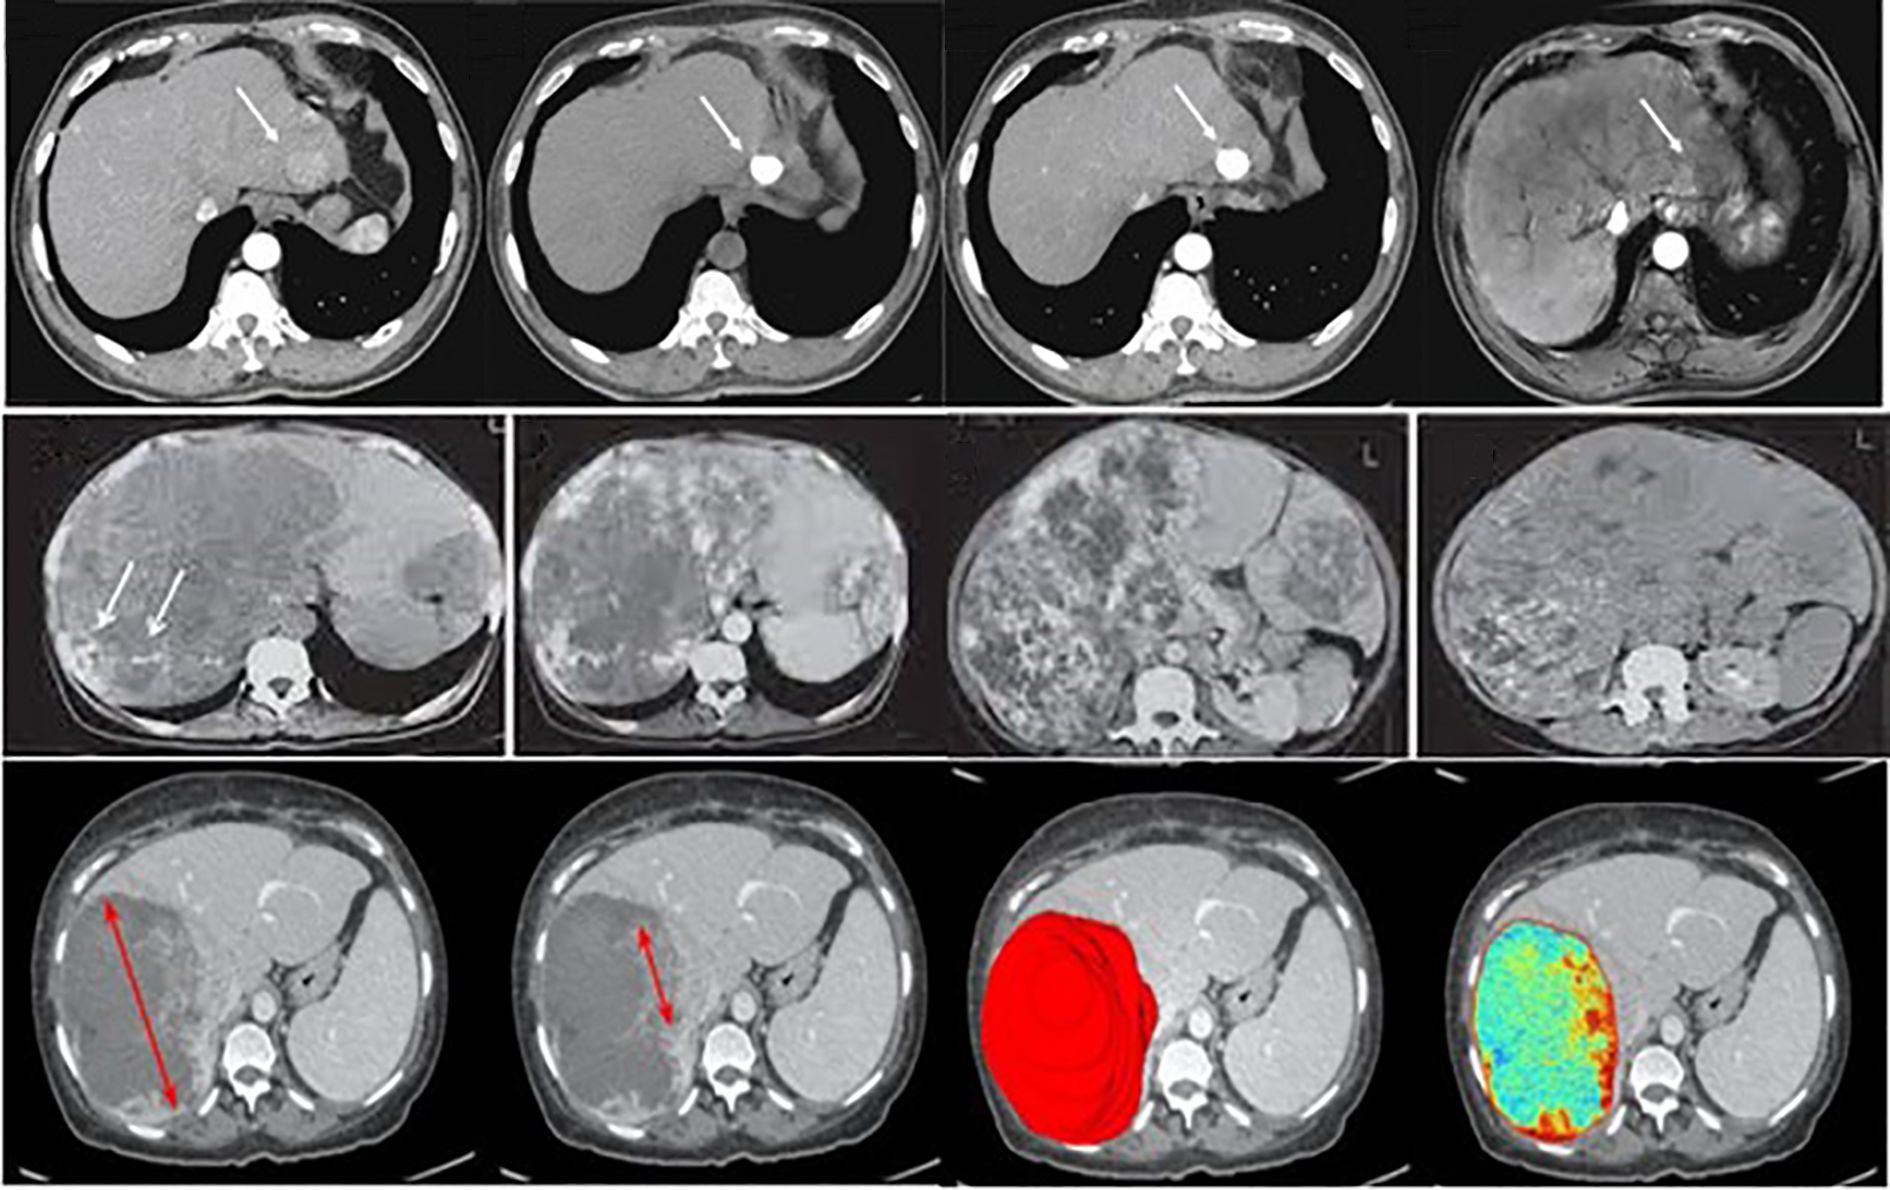

The dataset for this study assembles high-quality and variable medical imaging to help create an algorithmic forecast model for distinguishing and identifying liver cancer. Information was collected from online databases, Liver Tumor Segmentation (LiTS) Challenge dataset (https://www.kaggle.com/datasets/andrewmvd/liver-tumor-segmentation) and The Cancer Imaging Archive (TCIA) available at: https://www.cancerimagingarchive.net/. These datasets contain labeled CT and MRI scans necessary for evaluating liver tumors (23). Besides these sources, de-identified imaging data were recruited from partnering medical institutions; all patient data were anonymized in accordance with institutional review board (IRB) approval and national ethical regulations. Ethical approval was obtained prior to data transfer. To minimize potential bias, harmonization procedures were applied, including standardization of image resolution, intensity normalization across scanners, and exclusion of cases with incomplete metadata. These measures ensured that the multi-center dataset met essential ethical and methodological standards, while also increasing dataset size and variability to improve model robustness. The primary interest is given to primary liver cancer, mainly HCC; cases of secondary liver cancer and cases with poor image quality or missing images were also removed to ensure the high quality of input data. The dataset is categorized into three primary classes: Benign, Malignant, and Normal (Healthy Liver), which were used with equal sample sizes to reduce over-fitting by the model by incorporating a balanced data set. Before their analysis, measures include resizing the images to a particular dimension, normalizing the pixel intensity values, and enhancing image denoising to increase the uniformity of images. Pre-processing strategies like rotation, flipping, scaling, and applying contrast enhancement were used to improve the model’s robustness. The dataset was divided into three subsets: For example, in pattern identification, 80% of the data was used for training, while 10% was used for validation and 10% for testing. The division in partitions of training, validation, and training-m continents guarantees the model is trained on various samples; the separated evaluation set is immune to the influences of training. The training was performed over 20 epochs using the dataset of approximately 30k images for training and 5k for validation and testing. Where feasible, additional clinical metadata, including patient age, gender, and tumor stage, were incorporated to allow the potential integration of modalities for learning. Judging by the completeness and well-selected database and the well-organized classification system necessary for liver cancer identification and differentiation, Figure 3 shows sample images of Benign, Malignant, and Normal.

Figure 3

CT scan images of the liver show three rows of slices. The top row highlights a lesion with a white arrow. The middle row focuses on various liver conditions with white arrows. The bottom row includes scans with red arrows and colored overlays indicating differences in tissue density or pathology.

Figure 3. Examples of liver tumor images used in this study, illustrating the categories benign, malignant, and normal. (Top row – Normal liver tissue; Middle row – Benign lesions; Bottom row – Malignant lesions).